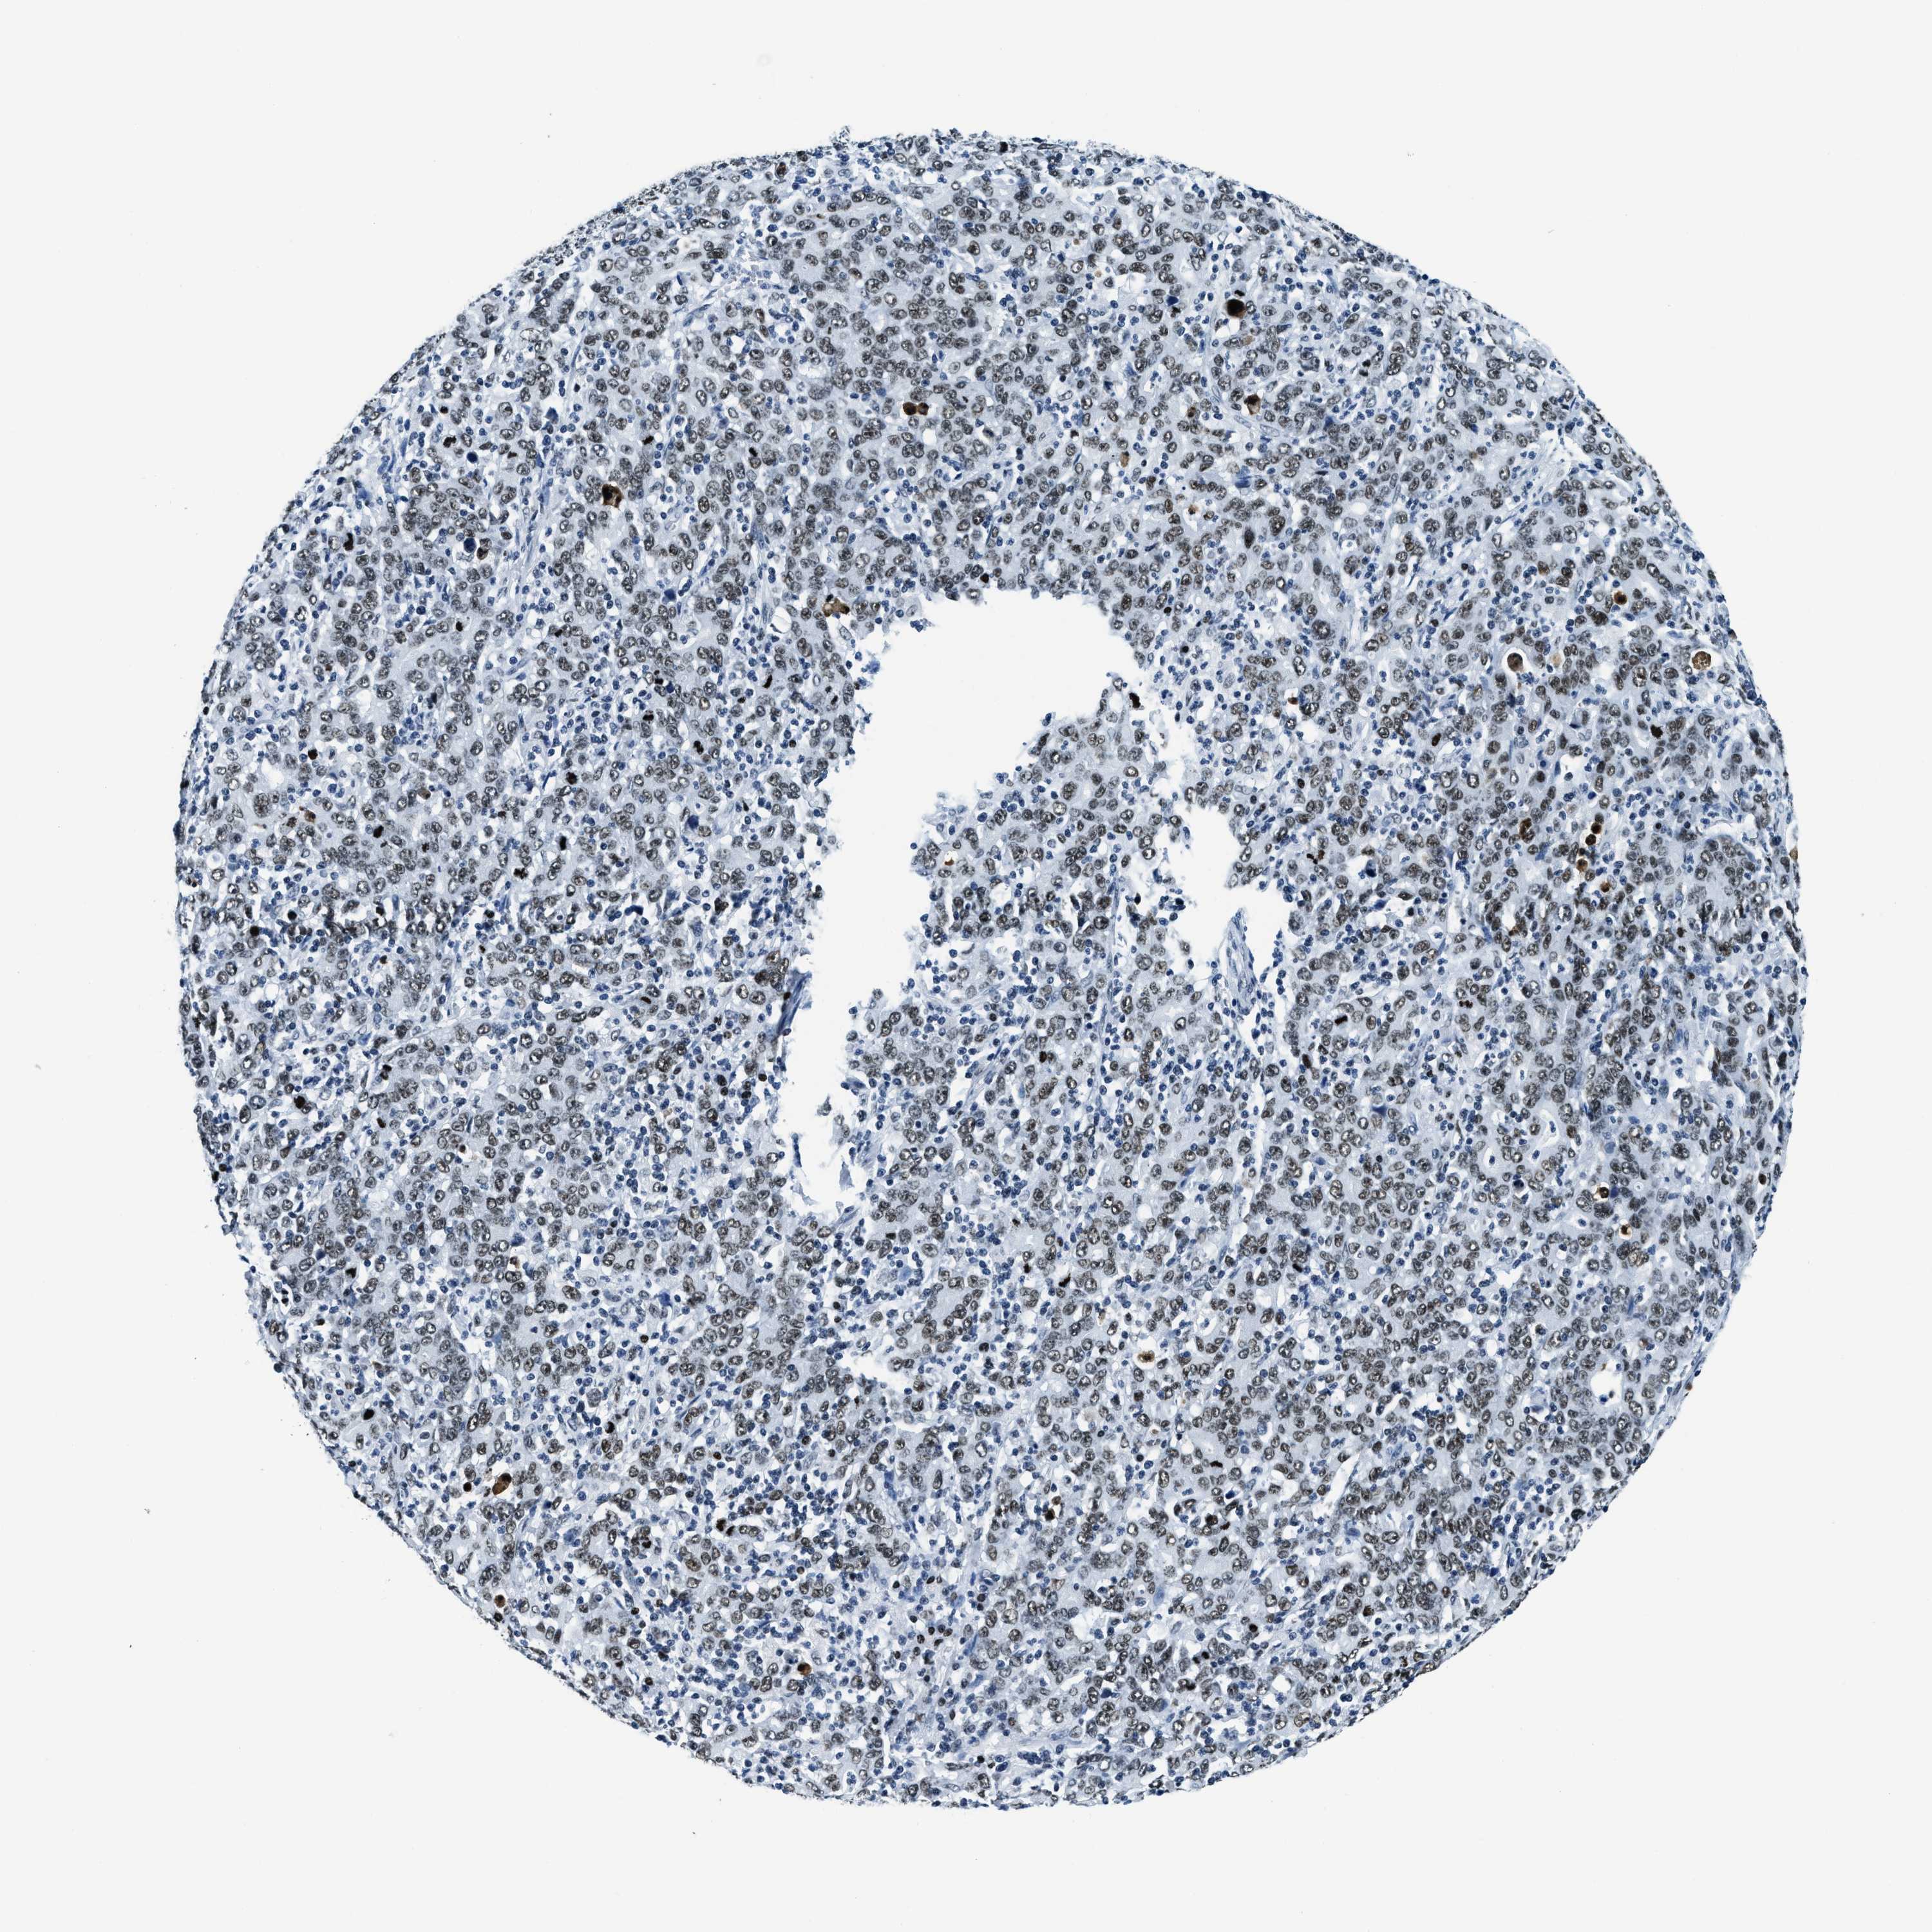

STOMACH CANCER - Protein expressioni

A mouse-over function shows sample information and annotation data. Click on an image to view it in a full screen mode. Samples can be filtered based on level of antibody staining by selecting one or several of the following categories: high, medium, low and not detected. The assay and annotation is described here.

Antibody stainingi

Antibody staining in the annotated cell types in the current human tissue is reported as not detected, low, medium, or high, based on conventional immunohistochemistry profiling in selected tissues. This score is based on the combination of the staining intensity and fraction of stained cells.

Each image is clickable and will lead to virtual microscopy that enables deeper exploration of all samples and also displays staining intensity scores, fraction scores and subcellular localization as well as patient and tissue information for each sample.

Antibody HPA019039

Antibody CAB009058

Staining

High

Medium

Low

Not detected

Intensity

Strong

Moderate

Weak

Negative

Quantity

>75%

75%-25%

<25%

None

Location

Nuclear

Cytoplasmic/membranous

Cytoplasmic/membranous,nuclear

Adenocarcinoma, NOS